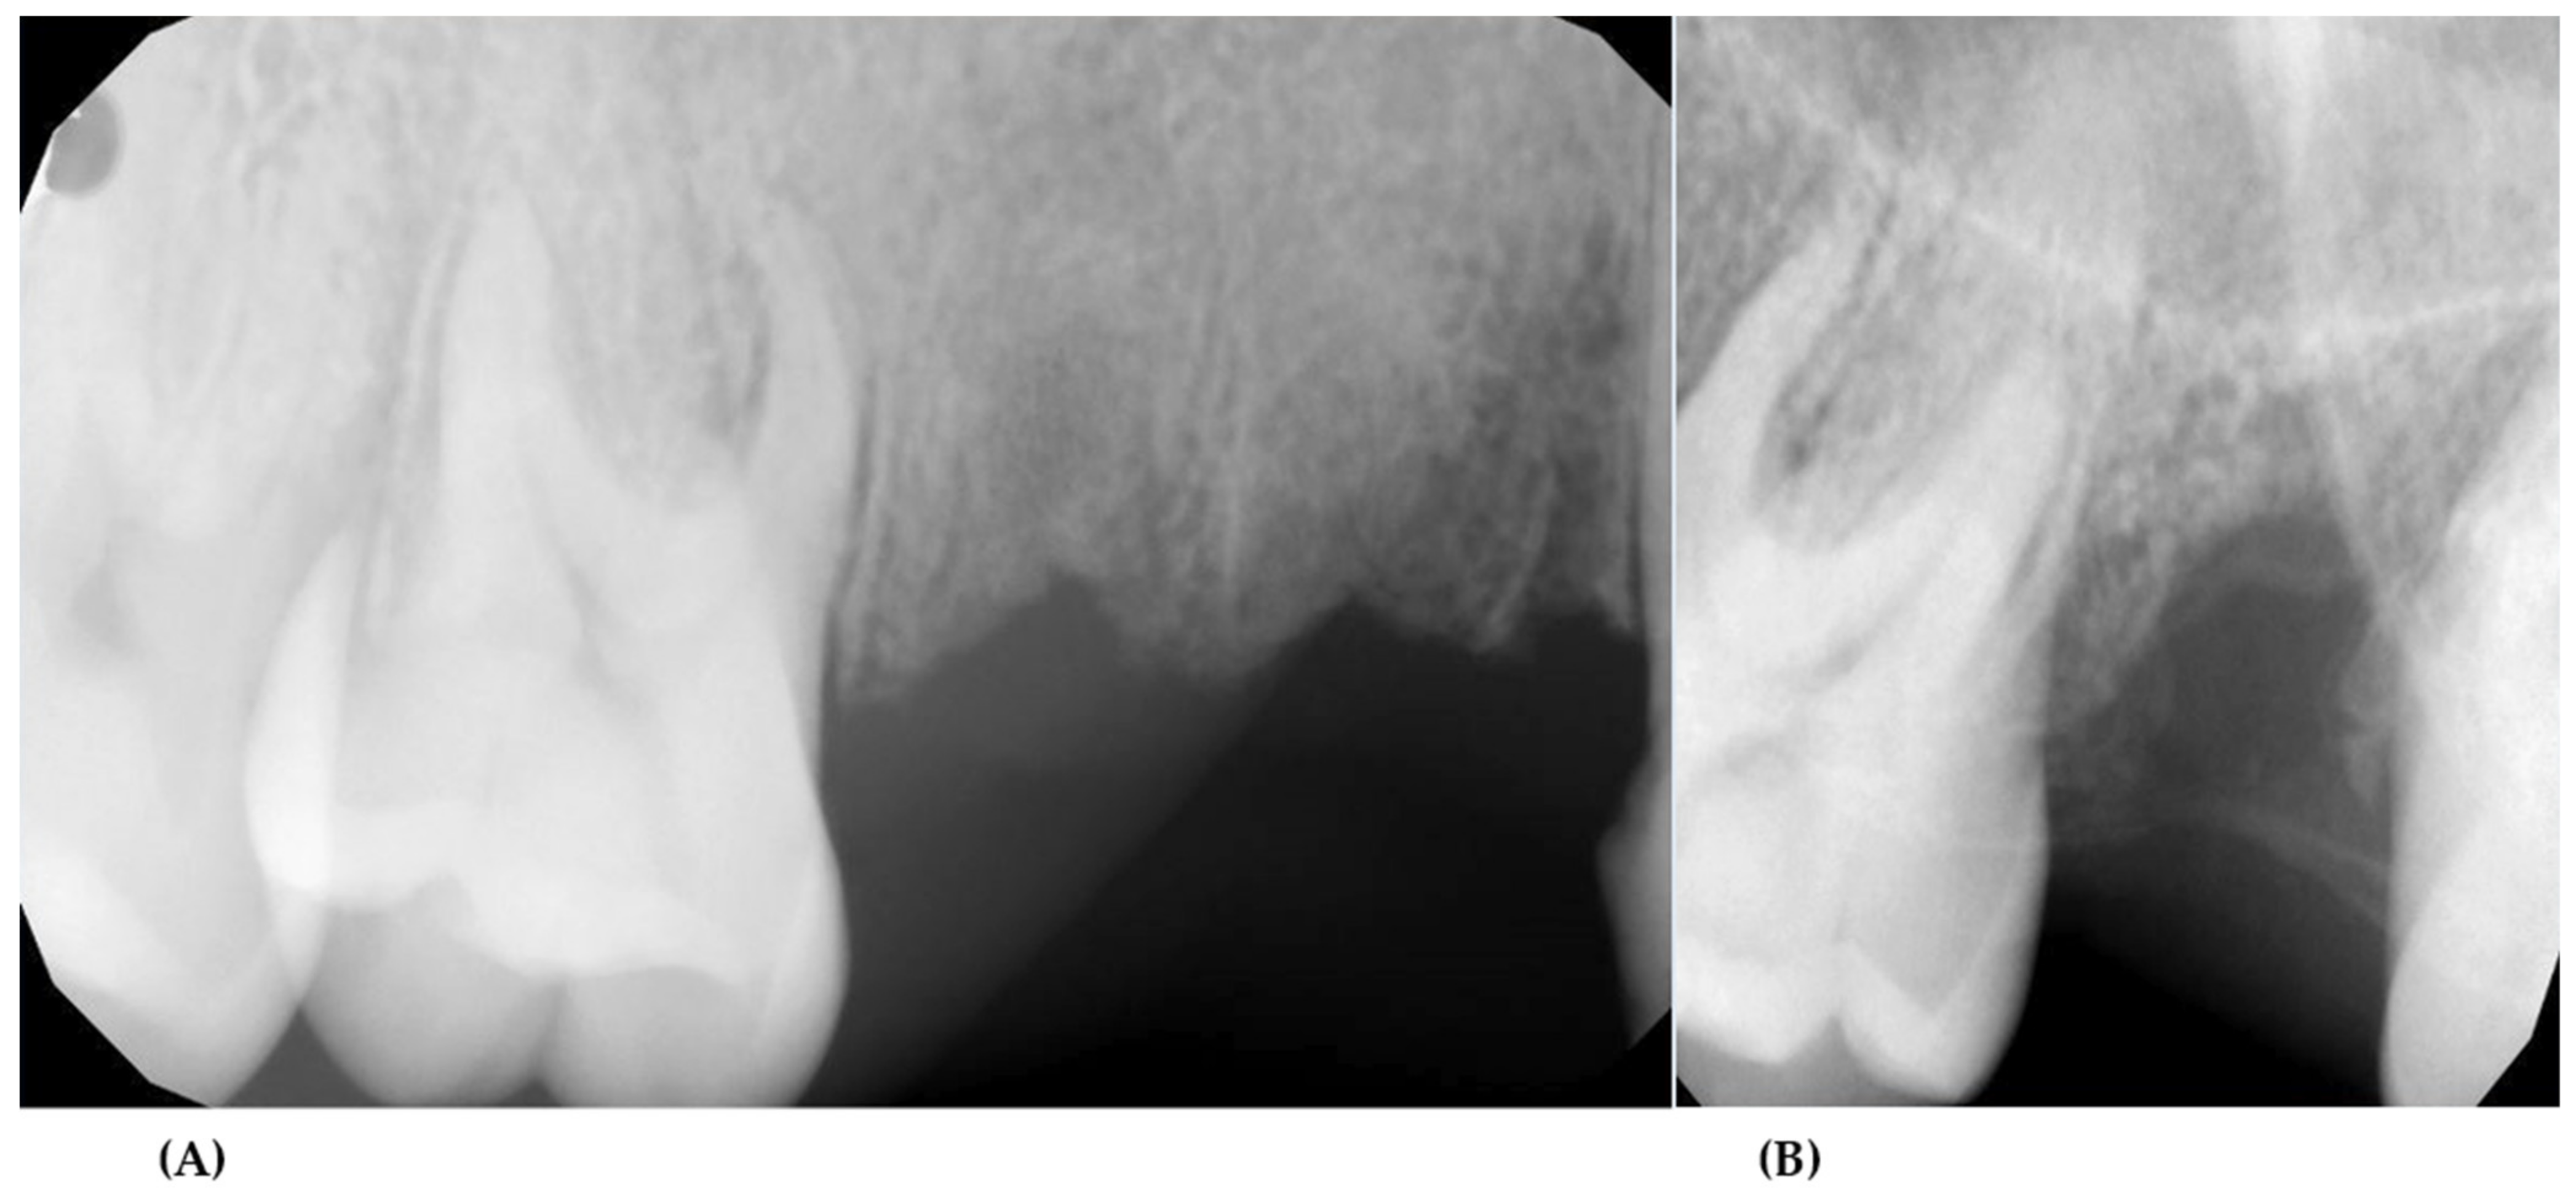

2. Case Presentation